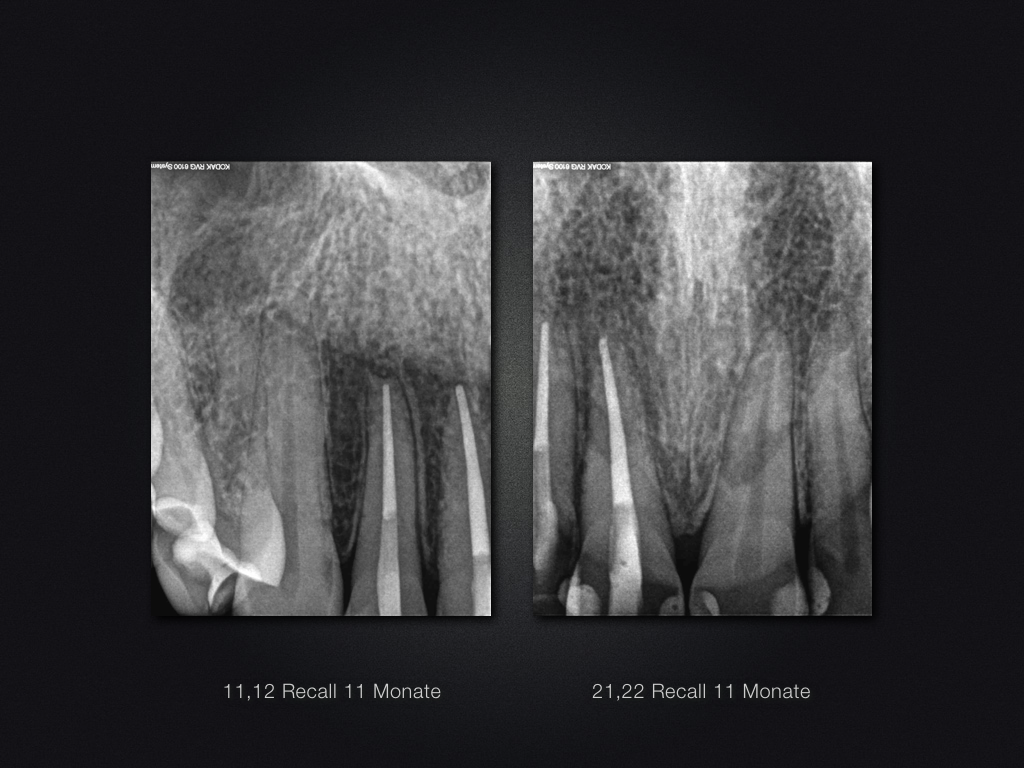

11 21 D Recall.015 Veröffentlicht 22. April 2017 am 1024 × 768 in Traumaspätfolge – knöcherne Ersatzresorption